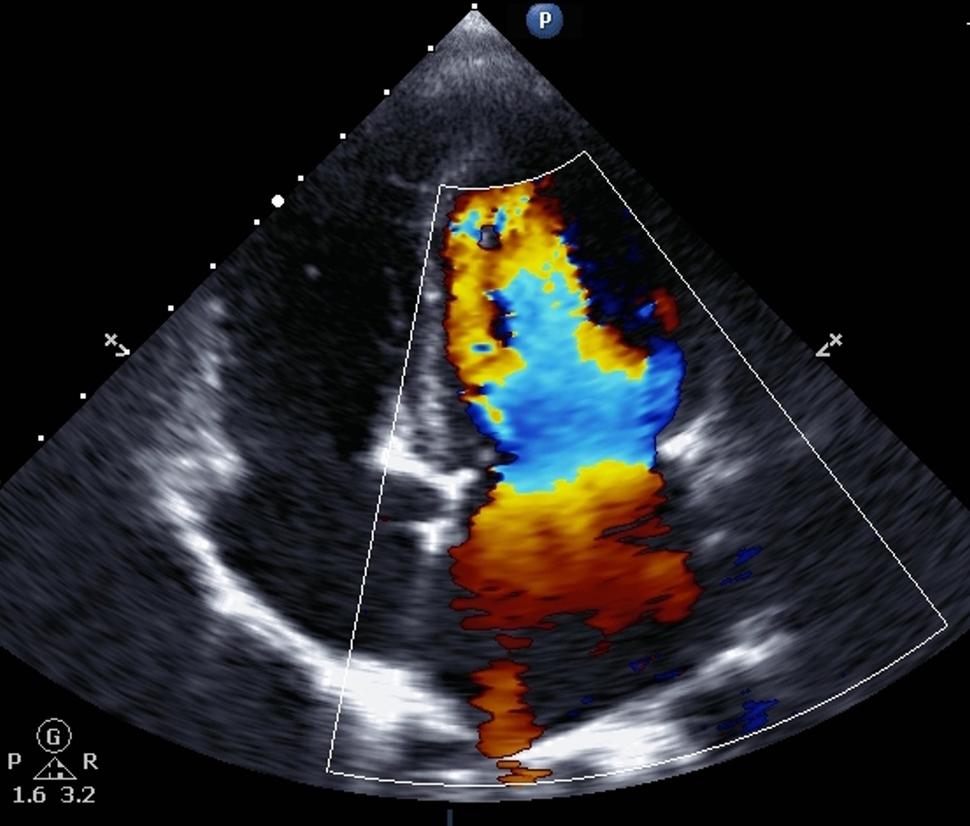

Una ecocardiografía Doppler

Una ecocardiografía Doppler (arriba) mide el flujo sanguíneo en el corazón. Según un nuevo estudio, administrar dexrazoxano (Zinecard) a los niños con cáncer antes de cada dosis de doxorrubicina disminuye el riesgo de problemas cardíacos relacionados con el tratamiento cuando son adultos.

Fuente: iStock